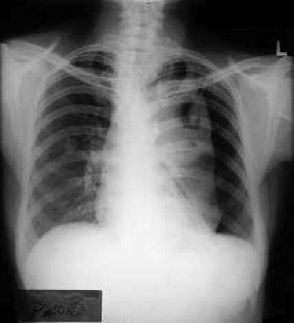

Describe the difference in appearance between inspiration and expiration chest films.

Need good inspiration for chest film. You should see first 10 ribs posteriorly and a breath in will lower the diaphragm. Without a deep inspiration the heart will look enlarged and the lungs will be condensed and more radio-opaque.

What condition is better demonstrated upon expiration than inspiration?

Pneumothorax – upright expiration is more sensitive. Look for mediastinal displacement. (Atelectasis maybe though too?)